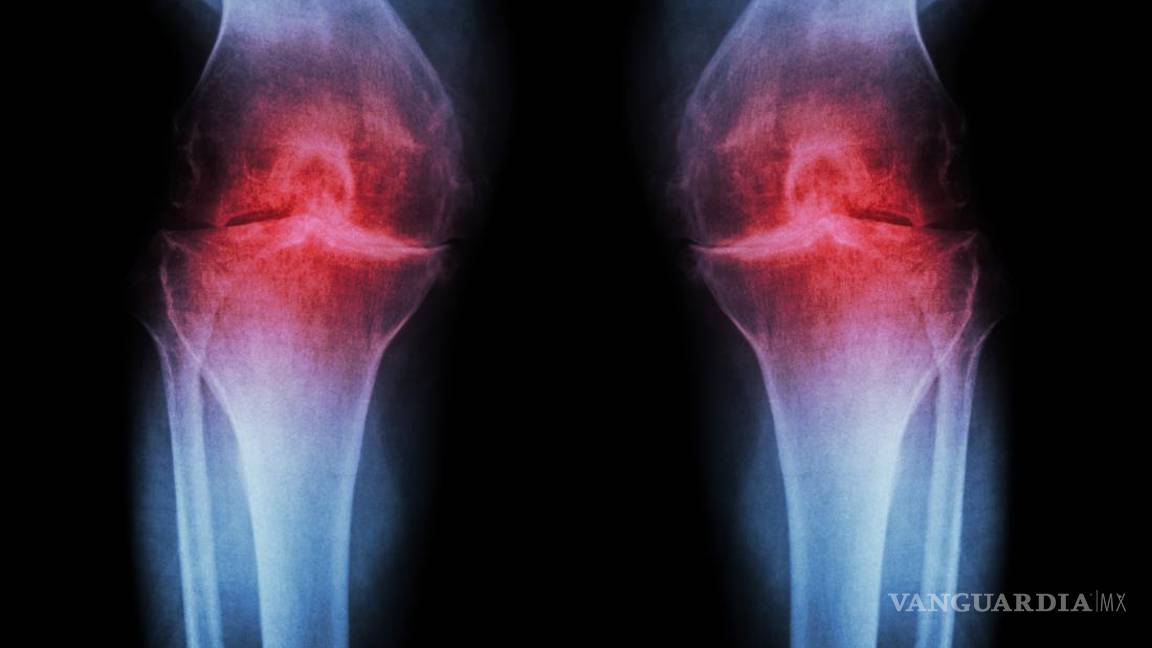

El sobrepeso genera mayor desgaste en las articulaciones

La osteoartritis es un padecimiento crónico-degenerativo que ocasiona destrucción gradual y progresiva del cartílago que cubre las rodillas, cadera, hombros, manos, tobillos y columna vertebral. A escala global, alrededor de 15 por ciento de la población mayor de 60 años de edad la padece y ahora cada vez más adultos jóvenes y de mediana edad desarrollan el padecimiento. Está comprobado que adultos entre los 22 y 55 años que experimentan este mal en cadera o rodillas son cuatro veces más propensos a sufrir altos niveles de estrés y depresión, además de que 67 por ciento reporta invalidez labo-ral, sostuvo.

La osteoartritis es considerada la más común de las enfermedades reumáticas crónicas. Entre estos padecimientos es de 10 a 12 veces más frecuente que la artritis reumatoide, con prevalencia en rodillas.